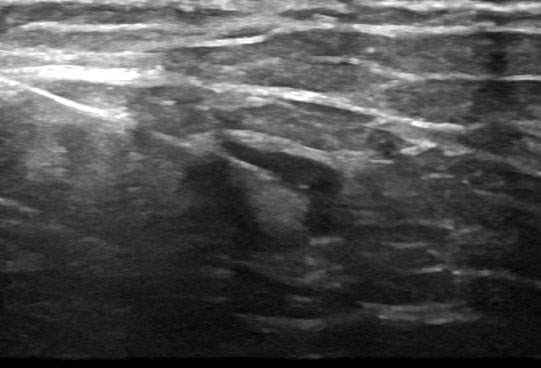

Prior to the procedure, a sonographer (ultrasound specialist) will check your details. Your examination will commence with a brief scan of the area by a sonographer who will then use what is called a transducer or probe to scan the area. The probe must be in direct contact with your skin to achieve adequate visualisation. The Radiologist will discuss the procedure with you prior to the biopsy. You are encouraged to ask any questions you may have. The Radiologist will locate the area to be biopsied and apply anaesthetic solution to your skin. Local anaesthetic is used to numb the area before a core biopsy, but this is often not needed in a fine needle aspiration. The procedure may be uncomfortable, but this is rare. If anaesthetic is required the Radiologist will ensure it has taken effect before the biopsy needle is placed into the area to remove a small sample of tissue. Often a number of samples are required. The doctor will inform you during the procedure how many samples will be required and which needle type will be used.